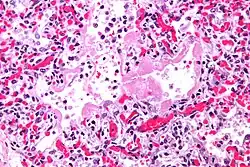

La neumonía intersticial aguda, también llamada síndrome de Hamman-Rich, es una enfermedad pulmonar poco frecuente de causa desconocida que se incluye dentro del grupo de las enfermedades pulmonares intersticiales. Aunque se llama neumonía, no tiene relación con las neumonías de origen infeccioso provocadas por bacterias o virus, mucho más frecuentes. Se inicia de forma brusca, generalmente en paciente de más de 40 años previamente sanos y cursa con tos, fiebre y sensación de falta de aire (disnea).[1][2][3]

El diagnóstico se sospecha por los síntomas y los estudios de imagen. En la radiografía de tórax aparecen opacidades difusas e irregulares en los dos pulmones que se conocen como en vidrio esmerilado. El diagnóstico de certeza precisa la realización de una biopsia pulmonar y un estudio histológico de la muestra. El diagnóstico diferencial abarca distintos procesos que pueden dar manifestaciones similares, entre ellos reagudizaciones de fibrosis pulmonar, neumonía eosinofílica, neumonía organizativa criptogenética, neumonía por Pneumocystis jirovecii, neumonitis por fármacos, neumonitis por hipersensibilidad e infección pulmonar por legionella.[2]